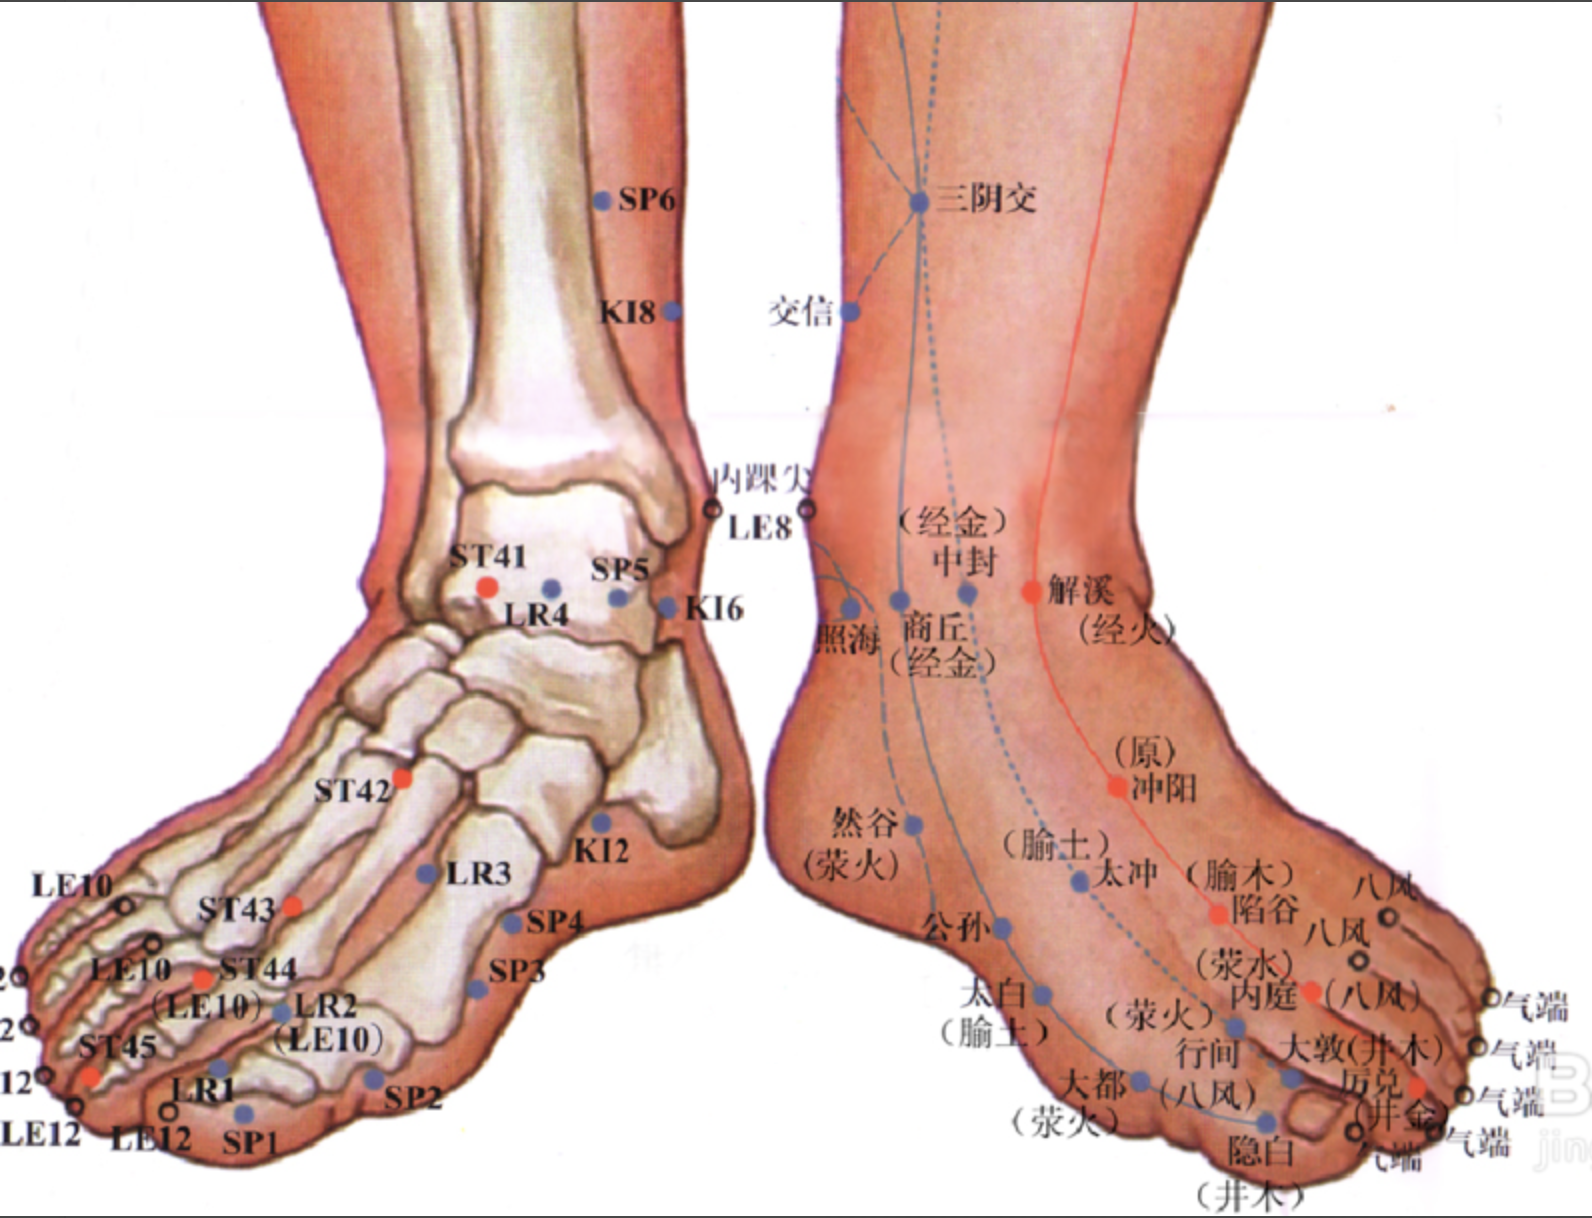

大敦

【定位】 在足大趾末节外侧,距趾甲角 0.1 寸。

【主治】 疝气,缩阴,月经不调,血崩,尿血,癃闭,遗尿,淋证,癫狂,痫证,少腹痛。

【配伍】 配内关、水沟治癫、狂、痫和中风昏仆,配膻中、天突、间使治梅核气。

【刺灸法】 斜刺 0.1 ~ 0.2 寸,或用三棱针点刺出血;可灸。

【附注】 肝经井穴。

行间

【定位】 在足背侧,当第 1、2趾间,趾蹼缘的上方赤白肉际处。

【主治】 月经过多,经闭,痛经,带下,阴中痛,遗尿,淋证,疝气,胸胁满痛,呃逆,咳嗽,洞泻,头痛,眩晕,目赤痛,青盲,中风,癫痫,瘛(chì)疭(zòng),失眠,口歪,膝肿,下肢内侧痛,足跗肿痛。

【配伍】 配睛明治青光眼、降眼压,配太冲、合谷、风池、百会治肝火上炎,头痛、眩晕、衄血,配中脘、肝俞、胃俞治肝气犯胃之胃痛,配中府、孔最治肝火犯肺干咳或咯血。

【刺灸法】 直刺 0.5 ~ 0.8 寸;可灸。

【附注】 肝经荥穴。

太冲

【定位】 在足背侧,当第 1、2跖骨结合部之间凹陷处。

【主治】 头痛,眩晕,疝气,月经不调,癃闭,遗尿,小儿惊风,癫狂,痫证,胁痛,腹胀,黄疸,呕逆,咽痛嗌干,目赤肿痛,膝股内侧痛,足跗肿,下肢痿痹。

【配伍】 配大敦治七疝,泻太冲、补太溪、复溜治肝阳上亢之眩晕,配合谷为开四关又治四肢抽搐,配肝俞、膈俞、太溪、血海治贫血、羸瘦,配间使、鸠尾、心俞、肝俞治癫狂痫。

【刺灸法】 直刺 0.5 ~ 0.8 寸;可灸。

【附注】 肝经腧穴、原穴。